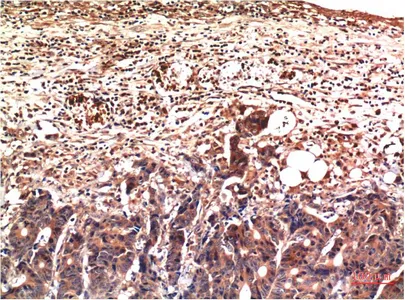

HER2(11H9)Mouse Monoclonal Antibody

Cat: AMM11986

Size1:50μL Price1:$118

Size2:100μL Price2:$220

Size3:200μL Price3:$380

Application:WB,IF-P,IF-F,ICC/IF,IHC-P

Reactivity:Human,Mouse,Rat

Conjugate:Unconjugated

Optional conjugates: Biotin, FITC (free of charge). See other 26 conjugates.

Gene Name:ERBB2